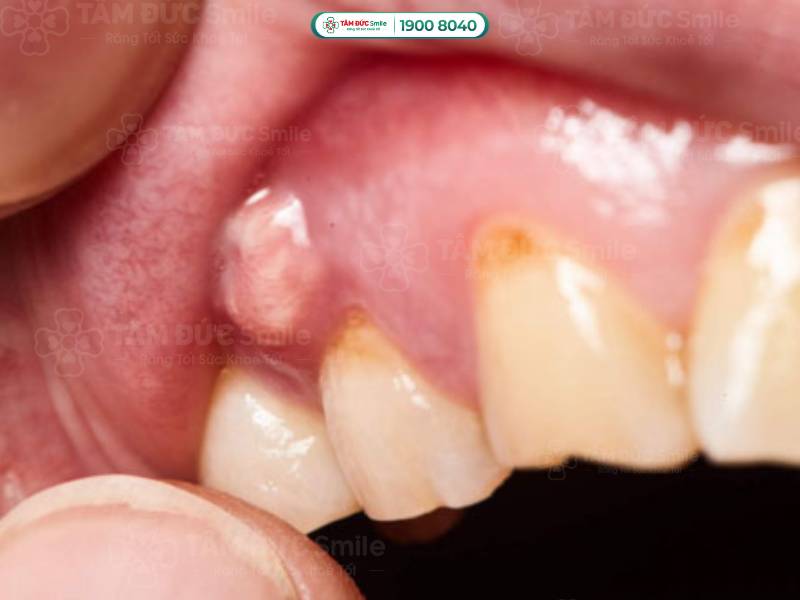

1.1.2. Áp xe chóp răng (áp xe chân răng)

Áp xe được hiểu là tập hợp mủ được hình thành từ các tế bào bạch cầu chết, vi khuẩn và những mảnh mô vụn. Vấn đề áp xe chóp răng bắt đầu từ tủy răng và kết thúc ở phần chóp chân răng.

Vấn đề áp xe chóp răng bắt đầu từ tủy răng và kết thúc ở phần chóp chân răng

Phần lớn các trường hợp áp xe chân răng là do sâu răng, răng bị sứt mẻ nặng gây tổn thương tới tủy. Ngoài ra, người bệnh viêm nướu, viêm nha chu cũng có nguy cơ bị áp xe chóp răng cao hơn. Bởi vì vi khuẩn phát triển dần vào chóp răng, gây viêm nhiễm, theo thời gian tiến triển thành áp xe.

Chứng áp xe chóp răng thường khó nhận biết bằng mắt thường. Người bệnh có những biểu hiện dưới đây nên đến thăm khám ở các cơ sở y tế để được chẩn trị chính xác:

- Đau nhức răng, người bệnh chỉ cần nhai nhẹ cũng có cảm giác đau.

- Ê buốt răng khi sử dụng các loại thực phẩm nóng, lạnh.

- Vùng áp xe có thể làm hành sốt, nổi hạch ở cổ, khiến người bị mệt mỏi.

- Phần lợi dưới chân răng bị sưng; khi soi gương, bạn có thể thấy hạt mủ tụ ở phần chân răng gây đau.